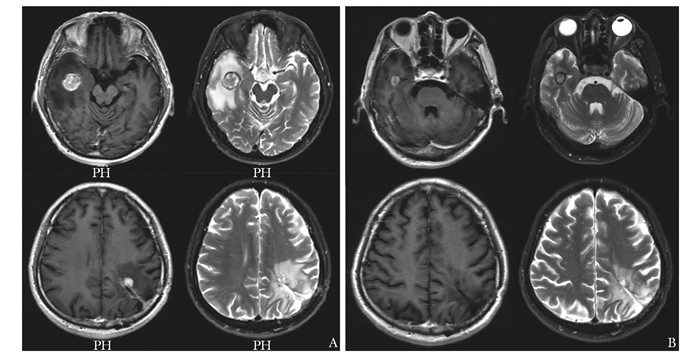

• 摘要: 肾细胞癌是泌尿系统中恶性度较高的肿瘤,常出现远端转移,尤其伴随中枢神经系统转移后,患者预后更差,临床管理困难,需多学科协作诊疗。本文报道一例肾透明细胞癌多系统转移患者,经北京协和医院肿瘤多学科协作团队(multidisciplinary team,MDT)5次会诊,得到个体化诊疗,并取得良好效果。通过对MDT讨论决策进行详细分析,可展现MDT在疑难重症病例诊疗方面的优势,有助于缩短治疗时间窗、打破科室界限、提高患者依从性、更好地制定符合循证医学理念的诊疗建议,为患者提供更加精准、个体化的临床管理方案。

Abstract: Renal cell carcinoma(RCC) is a type of tumor with a high degree of malignancy in the urological system, often with distal metastases, especially to the central nervous system. These patients are often endowed with poorer prognosis and more complex management that require a multidisciplinary team(MDT). This article reported a case of clear cell renal cell carcinoma with multisystem metastases.The MDT of Peking Union Medical College Hospital(PUMCH) discussed and formulated the optimal individualized treatment scheme for the patient, and achieved good results after 5 consultations. Through a detailed analysis of discussions and decisions of MDT, the advantages in the treatment of such difficult and serious cases are demonstrated, including shortening the time window of treatment, breaking down departmental boundaries, improving patients' compliance, developing treatment recommendations in line with the concept of evidence-based medicine, and providing more accurate and individualized clinical managements for patients.